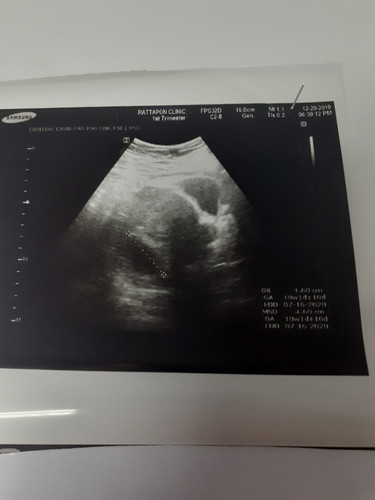

วันนี้หมอนัดซาว 9+4 วีค พบแต่ถุงตั้งครรภ์ ยังไม่เจอน้อง หมอนัดอีก1อาทิตย์ ไปซาวใหม่ มีแม่ๆคนไหนเคยเจอแบบนี้ไหมคะ ตอนนี้กังวลมากคะ กลัวลูกไม่อยู่กับเรา

อันนี้ซาวหน้าท้อง หรือซาวช่องคลอดค่ะ ของเราเจอน้อง 9 วีค ซาวช่องคลอดค่ะ แม่รอสัก 11 วีค ก็ได้นะคะ แล้วไปซาวใหม่